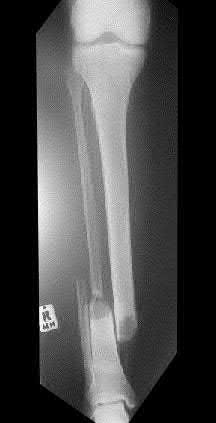

A 24-year-old male falls on an extended wrist. Radiographs are shown:

In Mayfield's progressive stages of perilunate instability, what is the final ligamentous structure to fail, resulting in a true lunate dislocation (Stage IV)?